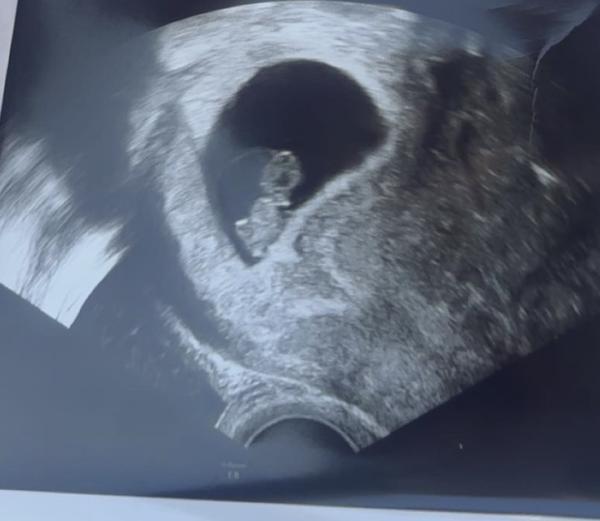

Hey,  ich bin mittlerweile in der 14. ssw, und ja ich kann meine Ausbildung im 3. lj. Ganz normal weiter machen. Es ist 4 Wochen her, seit ich mit meinen Freund getrennt bin und er erzählt halt sehr viel schlechtes rum, das er Nicht wusste das ich schwanger bin und ihm es erst erzählt habe als ich nicht mehr abtreiben konnte und ihm das kind unterjuble , ich bin so abgeschreckt von ihm-, weil ich niemals so etwas aus meinem Mundwerk kommen lassen würde.... Ja auch seine Eltern glauben das und bisher hat sich keiner gemeldet.

Bild zu

Antwort auf Beitrag von Babynr1.

Hey, vielen lieben Dank, dass du schreibst und das tolle Foto von deinem Baby schickst 🥰 Du schlägst dich wirklich sehr, sehr tapfer! Es ist bestimmt nicht leicht für dich, all diese Anschuldigungen zu ertragen. Und dass er so gar nicht würdigen kann, dass du das Baby in dir trägst, das genauso seines ist. Da fehlt ihm so ganz das Gespür... Da ist er aber nicht der einzige und so mancher Kindesvater hat sich im Lauf der Schwangerschaft oder wenn das Baby auf der Welt ist, besonnen und sich doch gefreut.  Deine Mama unterstützt dich weiter, oder?! Wer freut sich sonst noch mit dir?  Weiterhin viel Kraft und wachsende Freude auf dein Kleines 😊